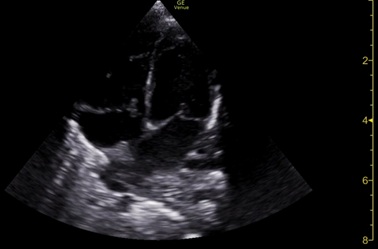

However, on day seven, frequent episodes of tachypnoea and desaturation after meals and a 20-mmHg systolic differential between upper and lower limbs were noticed, with poor perfusion. Echocardiogram demonstrated a dynamic left atrium, which was being compressed by the stomach (figures 6 and 7), with repeat diaphragmatic and abdominal ultrasound (figure 8) and thoracoabdominal contrast radiography (figure 9) showing recurrence of the hiatal hernia, prompting cessation of enteral feeds.

Figure 6: Echocardiogram on day 7, after a meal, showing left atria compression by the stomach (arrow).

Figure 7: Echocardiogram also on day 7, but now on food break, showing resolution of the left atria compression.

The newborn's hiatal hernia was diagnosed in the third trimester of pregnancy and was the first manifestation of his systemic disease. Bedside echocardiography, diaphragmatic, and abdominal ultrasounds during the first week of life showed intermittent hiatal hernia with intermittent compression of the left atrium. The increased gastric size after meals and consequent worsening of the stomach's protrusion to the chest cavity may be responsible for the desaturation, probably related to severe gastro-oesophageal reflux and subsequent aspiration. The blood pressure differential noticed between the upper and lower limbs was probably a consequence of the stomach's compression of the left atrium.